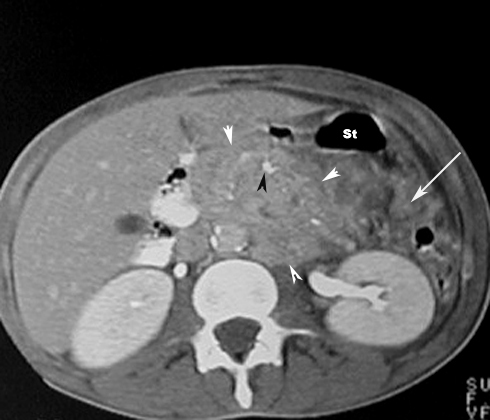

Acute Pancreatitis

Phlegmon / Inflammatory mass

• White arrowheads: Phlegmon

• Black arrowhead: Pancreatic calcification

• Large Arrow: Peripancreatic fascial infiltration

St: Stomach